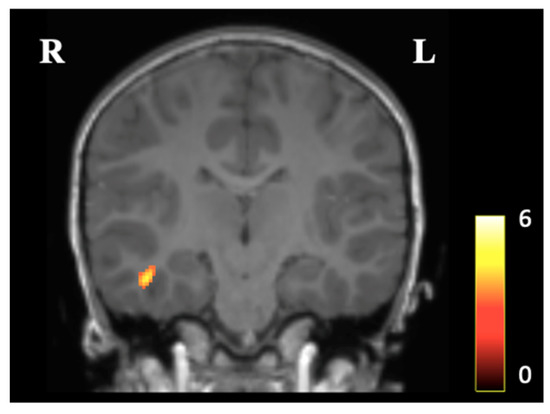

3.2. Voxel-Based Morphometry

3.3. Subcortical Gray Matter Volumes and Gray Matter Cortical Thickness